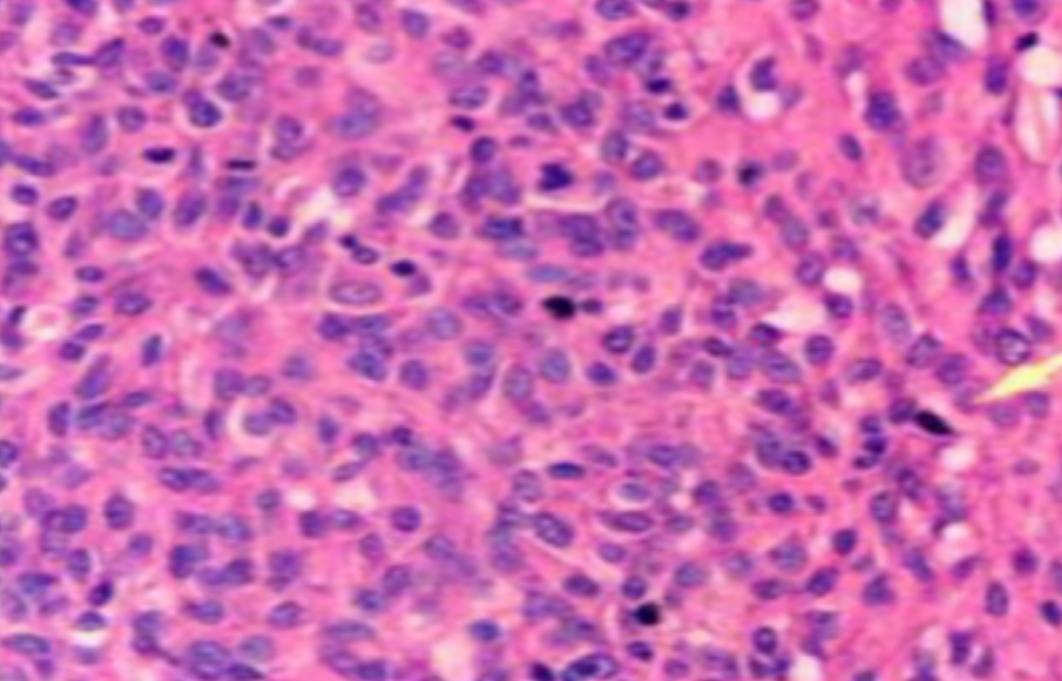

HE染色,全称苏木精-伊红染色法(Hematoxylin and Eosin staining),是最常见的组织切片染色技术之一,用于在显微镜下观察和分析组织或细胞的结构和形态。

虽然HE染色是最常见且最基础的染色技术之一,😭但在实验过程中,很容易出现各种情况导致染色切片质量参差不齐。所以,小编根据以往实验经验,给大家整理归纳出了15个HE染色中的常见问题,还包含问题原因分析以及解决方法哦~

形成原因:切片经梯度乙醇处理后没有完全脱水,导致二甲苯透明、中性树胶封固后残留大量水分。 解决方法:首先移去盖玻片,用二甲苯溶解封固剂如中性树胶,再将切片置入无水乙醇内,待切片重新脱水完全后,用二甲苯透明处理,中性树胶封固。要注意所有用于脱水和透明的液体,在使用一定时间后,应及时更换。 二、细胞核呈红、棕色 形成原因:苏木精染色液过度氧化,切片在苏木精染液染色后返蓝不足。 解决方法:每次染色之前检查苏木精染色液的染色能力,发现苏木精染色液氧化过度应及时更换。此外,切片经苏木精染色后,要给切片以足够的蓝化时间,蓝化过程可用流水、温水、弱碱性溶液(如稀氨水或0.2%碳酸氢钠)等处理。 三、切片在脱蜡后出现大片白色斑点 形成原因:由于烤(烘)片温度太低,切片上的组织蜡膜在脱蜡前没有充分烤(烘)融化。或是因为切片在二甲苯液中停留时间不足,或二甲苯使用过久,造成的脱蜡不彻底。 解决方法:若是由于切片烤(烘)温度低所致,可以先用二甲苯去除切片上的封固胶,然后重新用二甲苯脱去切片上的石蜡,再进行后续染色。若是由于切片在脱蜡的二甲苯中停留时间不足或脱蜡二甲苯使用过久浓度不足所致,则需将切片退回到二甲苯中,停留较长时间,或更换二甲苯液体重新脱蜡,再入乙醇重新脱二甲苯,入0.5%盐酸水溶液褪色后,重新HE染色。 四、细胞核苍白暗淡,即苏木精染色太淡 形成原因:切片在苏木精染色液停留时间太短;苏木精染色液过度氧化,失去染色能力,不能再继续使用;分化步骤处理时间过长;固定不及时。此外值得注意的是,若骨组织细胞核暗淡,大多是脱钙过度造成的。 解决方法:切片重新染色。如果组织在酸性固定液(如Zenker、Bouin)或非中性缓冲甲醛液固定时间过长,细胞核染色能力将减弱,需增加其在苏木精染色液的时间,或用一些方法增加组织的嗜碱性,以改善细胞核的着色。例如,上述组织玻片可以使用Weigert铁苏木精染色液。如果组织是用Zenker液固定的,可将切片脱蜡后放在5%碳酸氢钠溶液3~4h,流水冲洗5min后染色。如果组织是用Bouin液固定的,可将切片脱蜡后放在5%碳酸锂1h,流水冲洗10min后染色。 五、细胞核过染,苏木精染液占据了细胞质 形成原因:玻片在苏木精染色液停留时间过长,或是切片太厚、分化步骤时间太短。 解决方法:如果不是因为切片太厚(用显微镜仔细上下微调,只有一二层细胞核层次),就需将切片进行脱色、漂白、重新染色,适当调整染色和分化时间。但如果确定是由于切片太厚导致的细胞核过染,则需要重新切片。 六、伊红着色淡 形成原因:可能是伊红染液pH值大于5,也可能是蓝化液残留过多,切片太薄,或是切片经伊红染色后在乙醇脱水时间过长。 解决方法:检查伊红染液pH值,必要的话,用乙酸将其调节在4.6~5.0之间,从而使伊红染色色彩艳丽。此外,确保每次蓝化步骤完成后,使用的弱碱性溶液被充分洗去,玻片上没有残留的弱碱性溶液。最后,检查切片的厚度,且脱水时不要让切片在低浓度乙醇中停留时间过长,因为含水多的低浓度乙醇会将切片伊红的颜色分化掉。 七、细胞质过染、分色不足 形成原因:伊红染色液浓度太高,特别是存在焰红燃料、四溴四氯荧光素钠。切片在伊红染色时间过长,或是切片在伊红染色后经乙醇脱水步骤时时间太短,而使乙醇分化伊红的作用不能产生,都能够使细胞质过染。 解决方法:适当稀释伊红染色液,减少伊红染色时间,或使切片在乙醇脱水等步骤时,停留时间相对均匀。同样,也要检查切片的厚度是否合适。 八、切片中出现蓝黑色沉淀物 形成原因:苏木精染色液中的金属膜黏附在玻片上。 解决方法:染色前仔细过滤苏木精染色液,建议使用半氧化苏木精染色液,如Gill苏木精染色液,可以避免过多的金属膜产生。 九、光镜下切片某些区域难以聚焦 形成原因:盖玻片上可能有封固切片的封固剂。 解决方法:移去盖玻片,重新用干净的盖玻片封片。检查切片封片方法,是人工手工封法,还是机器自动封法,如有问题及时调整。 十、封固剂从盖玻片与载玻片之间的缝隙回缩 形成原因:盖玻片弯曲或不平整,或是封固剂含二甲苯过多,稀释过度。 解决方法:移去盖玻片,重新找一张盖玻片,用干净的封固剂封片。如用手工封片法,保证在封固结束时,封固剂容器盖子为紧闭状态。且尽量使用小的容器盛装封固剂,一旦封固剂太黏稠,就可以选择废弃。 十一、细胞核呈灰蓝状态 形成原因:可能由于组织处理温度过高、过热,在液体石蜡中停留的时间过长。或是固定时间太短后,直接在高浓度的乙醇中进行了脱水处理。 解决方法:理论上来说,仅在组织浸蜡步骤才进行加热,组织不能在热蜡液中停留太久。如果由于某些原因不能进行下一步包埋处理,可将组织连同塑料包埋盒一并放置在室温空气中,冷却凝固,以备包埋。待需要包埋时再重新加温直至石蜡融化即可。组织在处理前必须确保固定良好,脱水最好能从低浓度的乙醇开始。 十二、类色素的点状结晶和黑色光滑细胞核 形成原因:这种裸核改变是因为切片封片前放置在空气中的时间太长,以至于二甲苯挥发,切片干燥。 解决方法:移去组织切片上的盖玻片和封固剂,重新处理。将切片水洗数分钟,然后重新脱水、透明、封固。封片过程中要保持组织切片的轻度湿润,尽量不要让其干燥。 十三、染色过淡或过浓 解决方法:如果染色过淡,可以增加染色剂的浓度、延长染色时间或更换新鲜的染色剂;如果染色过浓,则应减少染色剂的浓度或缩短染色时间。 十四、切片出现叠加褶皱 形成原因:新购买的玻片洁净度不够、用镊子撑开切片时操作不够熟练未能平整伸展,或玻片表面有油脂,切片粘贴不牢。另外,烤片时间不足、烤片温度过低或切片过厚造成切片脱落,都会造成重叠或有皱褶的情况。 解决方法:新购买的玻片最好能用硫酸清洁液浸泡一晚,然后流水冲洗干净。在适宜的温度下烤片时间宁长勿短,保证有充足的烤片时间和温度。另外,切片刀要锋利,才能切出厚薄适宜的切片,保证切片不会因为过厚而脱落。 十五、组织残缺不全或有刮划痕迹 形成原因:组织残缺不全是由于切片时修整蜡块时深度不够、组织没有全部暴露于切面。切片的刮划痕迹是由于切片刀的刀锋有缺口、包埋的组织有异物,或是钙化组织、骨组织及包埋石蜡有沙粒造成的。 解决方法:修整蜡块时保证组织块全部暴露于切面,切片时保证切片刀的锋利没刀口。同时在组织取材时去除手术异物和钙化组织。最后,骨组织要完全脱钙,这样可以保证切片的完整和平整美观。 *注:由于实验中导致结果出现误差的原因多种多样,以上内容仅供参考,具体根据实际情况进行判断。